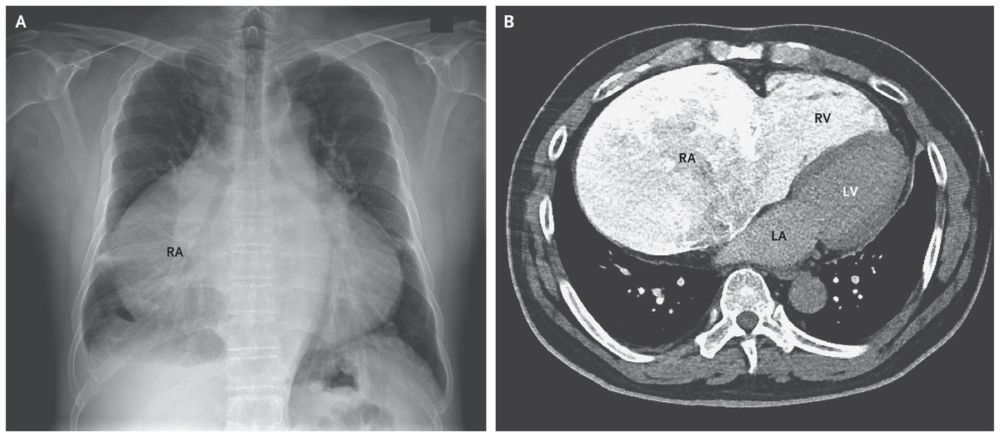

A radiograph of the chest showed a high cardiothoracic ratio of 0.82 and a very large right atrium (RA; Panel A).

Transthoracic echocardiography, cardiac computed tomography (Panel B), and cardiac magnetic resonance imaging revealed a giant right atrium, a dilated right ventricle (RV) with preserved systolic function, grade 4/4 functional tricuspid regurgitation, high-normal right-ventricular systolic pressure, and normal size and function of the left ventricle (LV). LA denotes left atrium. No shunt was identified.